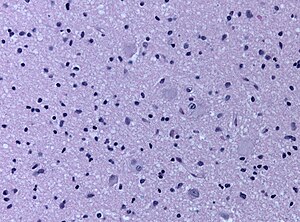

Micrograph showing a cortical tuber. H&E stain. (WC/jensflorian

Cortical tubers are malformative lesions in the CNS observed in tuberous sclerosis complex (abbreviated TSC), an autosomal dominant syndrome.

• Cortical tubers are malformative, epilepsy-associated.[1]

• Seen in 80-90% of the TSC cases.

• Gyrus is usu. thickened, raised, and occasionally dimpled.

• Giant cells, dysmorphic neurons, gliosis, calcifications.

• Prominent cell loss in all cortical layers.[2]

• Normal cortical lamination is lost in the lesion.

• TSC2 has larger and more numerous tubers.[3]